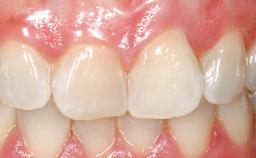

A 33-year-old female patient presented with an upper left central incisor that required extraction after a failed endodontic therapy. The tooth had been traumatized when the patient was a teenager and had undergone several endodontic treatments, including two apicectomy procedures. The patient was in good health and did not smoke. Clinical examination showed that the patient had a high lip line. In full smile, the gingival margins of the upper teeth were visible to the first molars. The gingival margins of central incisors 11 and 21 were only just showing. Examination of tooth 21 confirmed that the tooth was mobile and had hypererupted by 1 mm.

Lip Line No exposure of papillae Exposure of papillae Full exposure of mucosa margin

Periodontal Phenotype Low-scalloped, thick Medium-scalloped, medium-thick High-scalloped, thin

Shape of Tooth Crowns Rectangular Triangular